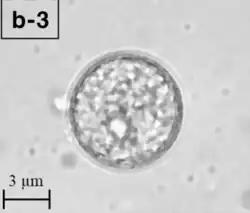

A Balamuthia mandrillaris cyst

B. mandrillaris is a free-living, heterotrophic amoeba, consisting of a standard complement of organelles surrounded by a three-layered cell wall (thought to be made of cellulose or a similar polysaccharide[8]), and with an abnormally large cell nucleus. On average, a Balamuthia trophozoite is about 30 to 120 μm in diameter. The cysts fall around this range, as well.[9]

Balamuthia's lifecycle, like the Acanthamoeba, consists of a cystic stage and a non-flagellated trophozoite stage, both of which are infectious, and both of which can be identified in the brain tissue on microscopic examination of brain biopsies performed on infected individuals. The trophozoite is pleomorphic and uninucleated, but binucleated forms are occasionally seen. Cysts are also uninucleated, possessing three walls: an outer thin irregular ectocyst, an inner thick endocyst, and a middle amorphous fibrillar mesocyst.[10]

Biopsies of skin lesions, sinuses, lungs, and the brain can detect of B. mandrillaris infection. The amoeba cannot be cultured on an agar plate coated with E. coli because, unlike Naegleria or Acanthamoeba, Balamuthia mandrillaris does not feed on bacteria. Instead, Balamuthia must be cultured on primate hepatocytes or human brain microvascular endothelial cells.[15] Formalin-fixed paraffinized biopsy specimens may indicate Balamuthia trophozoites in the perivascular space. The cysts can be visualized by calcofluor white, which binds to polysaccharides on the cyst wall. Trophozoites appear circular during infection.[14]